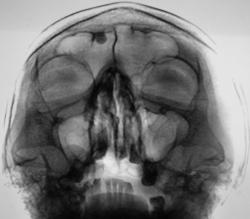

Иллюстрации 1, 2. На цифровой флюорограмме придаточных полостей носа, произведенной в прямой стандартной проекции в носо-подбородочном положении, в лобной пазухе, больше справа определяется тень значительной интенсивности, с довольно ровными, четкими контурами, однородной структуры. Интерпретация данной тени сложности не вызвала, так как по своим скиалогическим характеристикам представляет типичную остеому, а с учетом «излюбленной» локализации, дифференциально – диагностических трудностей не возникло.

.........."Иллюстрации 1, 2. На цифровой флюорограмме придаточных полостей носа, произведенной в прямой стандартной проекции в носо-подбородочном положении, в лобной пазухе, больше справа определяется тень значительной интенсивности, с довольно ровными, четкими контурами, однородной структуры. Интерпретация данной тени сложности не вызвала, так как по своим скиалогическим характеристикам представляет типичную остеому, а с учетом «излюбленной» локализации, дифференциально – диагностических трудностей не возникло."..... Как все догадались, это цитата из выше опубликованного поста ув. Валентина Львовича, она также подходит и к моему наблюдению.